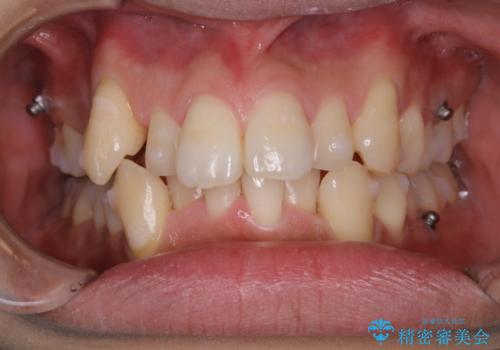

- インビザラインでの矯正治療中に、アタッチメント周囲のステインが気になるとのことでした。PMTC30分コースで、特に見える表側のステイン除去を行いました。

矯正治療中もPMTCを定期的に行い、専門的な機械でしっかりと汚れを除去することがおススメです。

30分コースでは主に前歯をメインに行います。